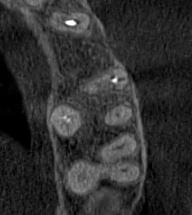

Отримайте вичерпну інформацію про стан ЛОР-органів завдяки надточній діагностиці на апараті

PLANMECA. Наші знімки дозволяють детально візуалізувати всі групи навколоносових синусів,

структури остіомеатального комплексу та анатомію носової перегородки.

Ми надаємо не просто знімок, а повний діагностичний сервіс:

Детальний опис: Кожне дослідження супроводжується професійним висновком лікаря-рентгенолога

з описом виявлених патологій (кісти, поліпи, сторонні тіла, рівень рідини, потовщення

слизової).

Зручна візуалізація: Можливість перегляду структур у будь-якій проекції (аксіальній,

корональній, сагітальній) для точної локалізації запального процесу.